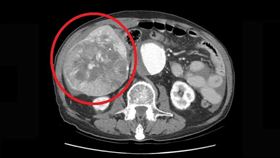

致死率高、初期無症狀 肝癌6大徵兆

近3、40年來,肝癌都在台灣十大死因排行榜上名列前茅...

晚期肝癌治療現曙光 新標靶藥物擺脫

台灣肝癌醫學會理事長、林口長庚胃腸肝膽科系教授級主治...

造福肝苦人!二線口服標靶接軌延命

根據衛福部十大癌症死因統計,肝癌不僅位居第二,且每年...